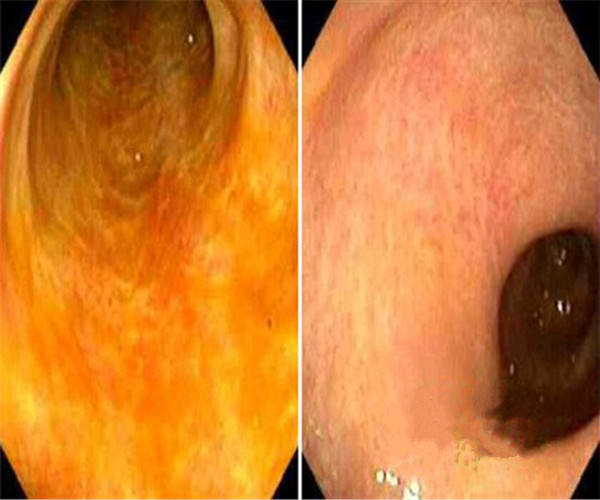

輕微潰瘍性結腸炎前後對比